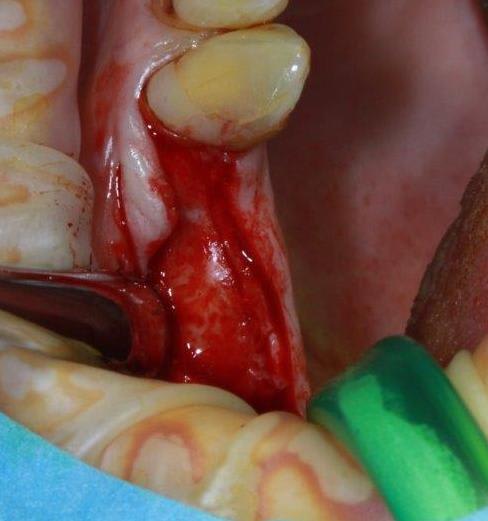

un petit cas pour ressortir ce post...et parce que c'est quand même chaud

incision crestale lame n°15, tatum, spreader Meissinger implants, PX34120 et OP34100 (summer avec eponges)

Ce qui me la coupe c'est que tu fais ça avec une incision vraiment minimale ( tu travailles au toucher ? :) ) .

oui, tout en sensations, et après avoir bien réfléchis sur le scan; c'est tout le principe de la manipulation osseuse, procédé qui semble voué à la disparition, avec les guides et les système GPSoguidés...en tout cas pour le moment, je prends mon pied à bricoler...